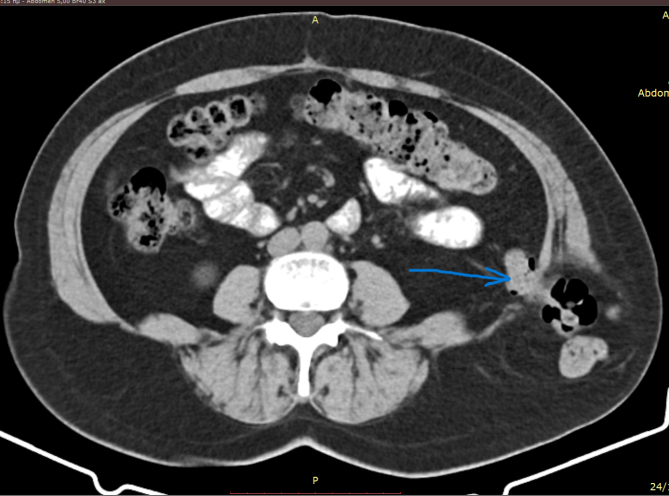

CT. Σημαντικό αιμάτωμα εκτεινόμενο στον προκυστικό χώρο (Ευγενική παραχώρηση Dr. V. Penopoulos).